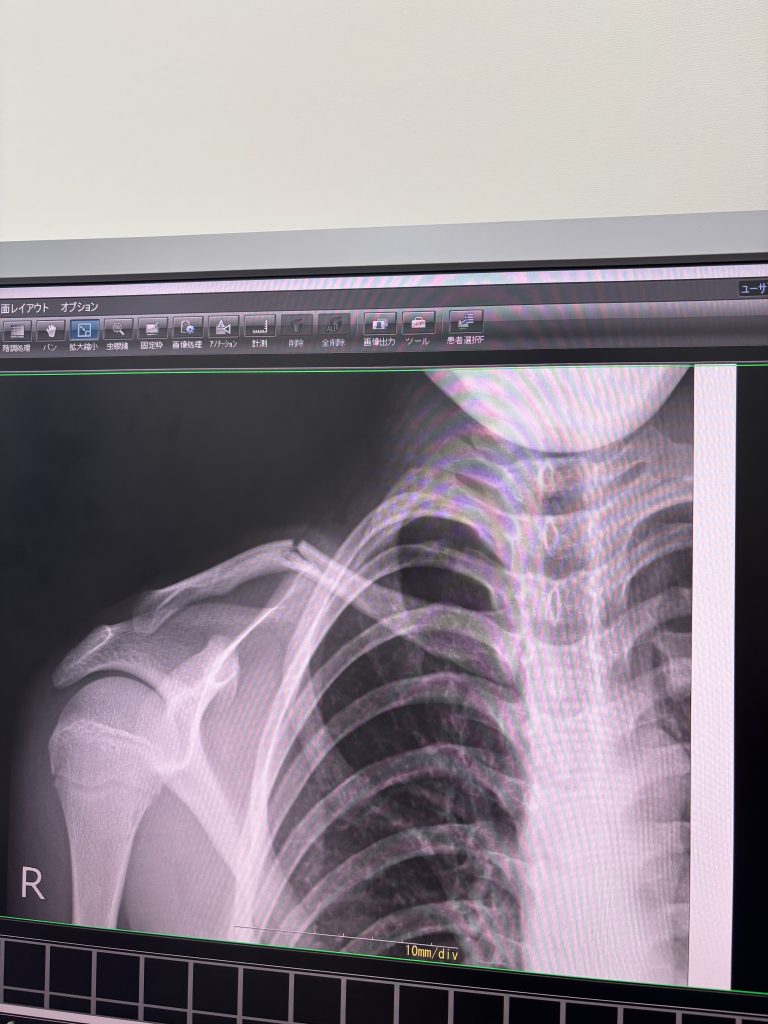

④そしてサッカー練習中に鎖骨を骨折して、来週の県大会も中学最後の試合も出れなくなって落ち込んでる次男くん。😢

見てください。ぽっきりいっちゃってます。

毎日動くたびに痛がってます。